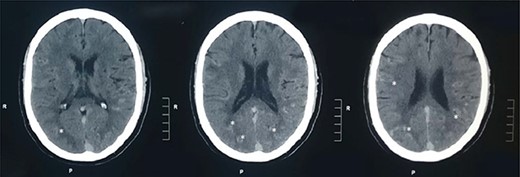

A 60-year-old male presented to our institute in the emergency department with a history of loss of consciousness for 20 minutes followed by aphasia, seizures and left-sided hemiparesis without any prior similar history. He was a known case of hypertensive for four years but was not under any medication. He was a regular consumer of homemade alcohol and consuming 250–500 ml/day. He did not have any other significant past medical or surgical history. On examination, he had a Glasgow coma score of 10/15 with normal pupils. Neurological examination revealed normal power in right upper limb with decreased power in the bilateral lower and left upper limbs. His other systemic examinations were normal; however, he was still hypertensive. Plain computed tomography (CT) of the head showed multiple linear areas of hyper-densities (mean attenuation ~50 HU) along cortical sulci of bilateral temporo-parieto-occipital lobes that mimicked subarachnoid hemorrhage (SAH) owing to its distribution pattern and presentation but did not qualify strongly as a SAH because of its marginal attenuation (Fig. 1) and hence was admitted to the neurosurgery intensive care unit with a risk of deterioration. Electroencephalogram (EEG) showed interictal EEG with an intermittent slow wave in theta region with alpha activity on the background (Fig. 2). With inconclusive diagnosis and suspicion of vascular malformation, he was advised for digital subtraction angiography (DSA) of cerebral arteries. Owing to the DSA unavailability at our institute and economic constraints of the patient denying any referral for invasive vascular imaging and intervention, he counseled to undergo dynamic CT angiography (CTA) for further evaluation. CT cerebral angiography revealed features consistent with DPCA (Fig. 3). Owing to this diagnosis, conservative treatment with antiepileptics and antihypertensives was chosen over the neurosurgical intervention. He slowly regained function with return of his voice and carried out normal day-to-day activities. His hospital stay was uneventful and was later discharged on oral medications.

Plain CT head: plain CT head (axial sections) at the level of lateral ventricles show multiple linear areas of hyper-densities along cortical sulci of bilateral temporo-parieto-occipital lobes (shown by asterisks).